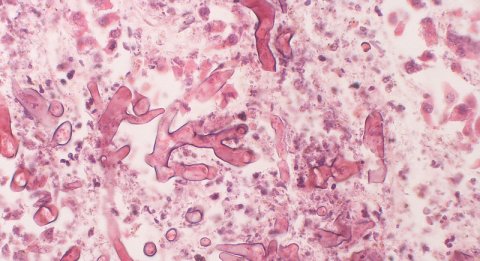

The hyphae of the causative fungus are non-pigmented. However, the older colonies become grey to brown in colour due to the development of pigmented spores. Nevertheless, the name "black fungus disease" comes from the black discolouration of the necrotic tissue that the fungus causes by invading blood vessels and destroying surrounding tissue. Mucormycosis rapidly involves neighbouring organs and can be fatal.

![Black necrotic area of a patient affected by mucormycosis. [Photo taken with consent of patient]](https://www.rstmh.org/sites/rstmh/files/styles/nugget-mobile/public/content/paragraphs/text/images/2021-08-18/4.jpg?itok=3RLlCpnR×tamp=1629315353)